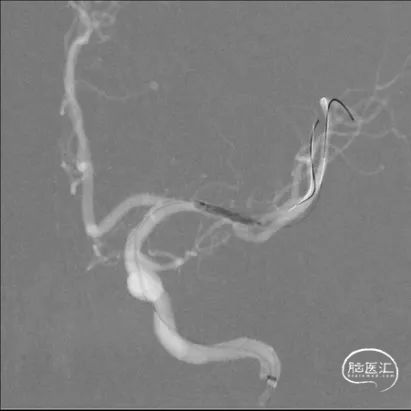

缓慢扩张球囊,球囊成形好。

球囊扩张过程

在大脑中动脉M1末端及上干起始段置入赛诺神畅 颅内药物支架NOVA DES®2.25*10mm,球囊扩张成形,支架成形好,狭窄处扩张好,下干未闭塞。

支架释放

术中将Navien导管送至颈内动脉岩骨段,增加支撑力,将两条微导丝分别送入左大脑中动脉上下干,先沿上干微导丝送入球囊扩张,效果差, 再沿下干微导丝送入球囊扩张,效果仍差,大脑中动脉M1末端狭窄有改善,但狭窄仍较重,遂用赛诺神畅 颅内药物支架NOVA DES®2.25*10mm置入左大脑中动脉M1末端及上干内,球囊扩张成形,支架成形好,血管成形满意,确定下干无闭塞后,撤出下干微导丝。